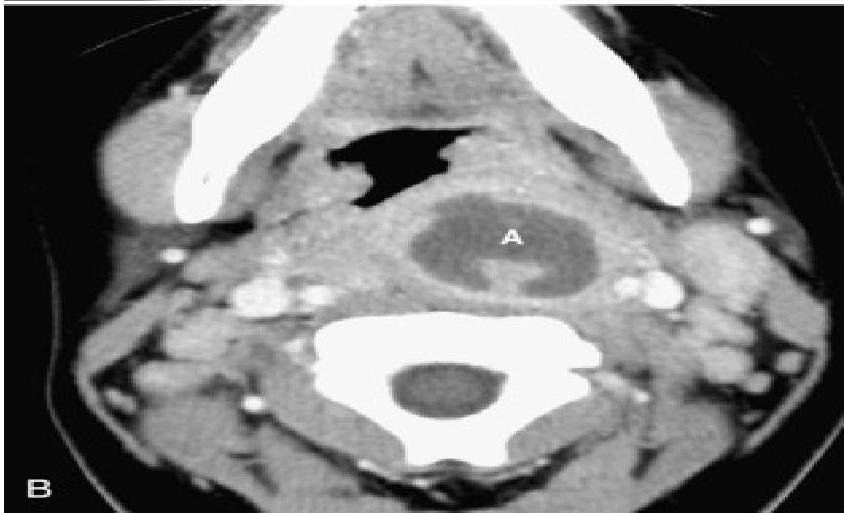

- Soft-tissue Lateral Neck Radiographs:

- Feature: An enlarged epiglottis protruding from the anterior wall of the hypopharynx (the “thumb sign”).

- Other findings: Thickened aryepiglottic folds, loss of vallecular air space, distended hypopharynx.

- Direct Visualization: Preferred if clinical suspicion is high. Performed during airway management in the operating suite. Shows a swollen, cherry-red epiglottis with an endotracheal tube passing posteriorly.